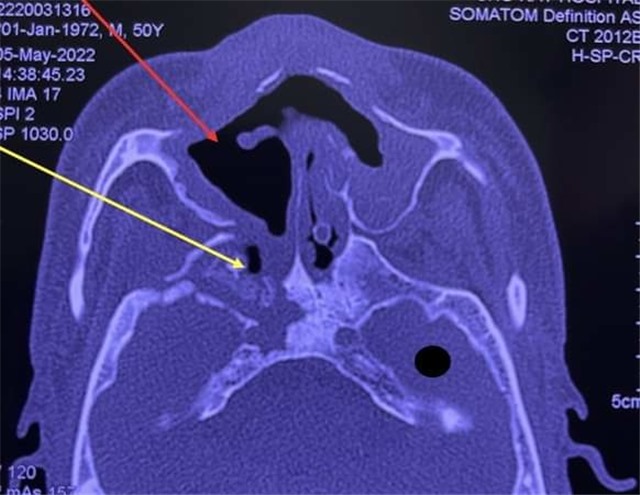

Bệnh viện Răng hàm mặt Trung ương TP HCM tiếp nhận 16 bệnh nhân, Bệnh viện Tai Mũi Họng điều trị 5 người hoại tử xương hàm, kể từ đầu năm đến nay.